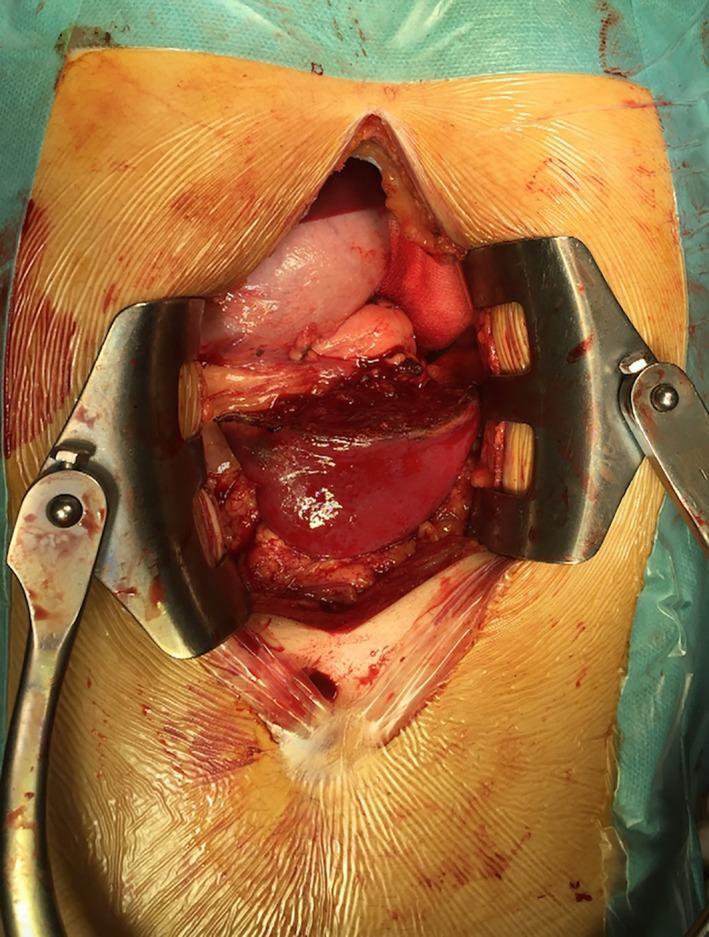

Partial splenectomy for a giant epidermoid cyst of the spleen.

The splenic epidermoid cysts are rare benign tumors, and a definitive treatment remains unclear. Although some spleen-preserving approaches have been reportedly used, splenic cyst recurrence usually occurs in true cyst cases, wherein the cyst is incompletely removed. In our case, partial splenectomy was performed and the giant cyst was completely removed.